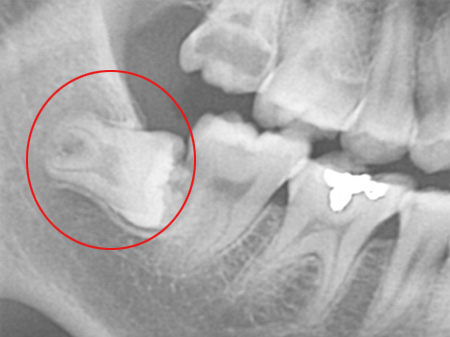

¸Åº¹ »ç¶û´Ï´Â ÅλÀ¿¡ °ø°£ÀÌ ÃæºÐÇÏÁö ¾Ê¾Æ »ç¶û´Ï°¡ ÀÕ¸öÀ» ¶Õ°í ¸ÍÃâµÇÁö ¸øÇϰí Ä¡Á¶°ñ ³»¿¡ ¸Åº¹µÈ °ÍÀ» ¸»ÇÕ´Ï´Ù. ÀÌ ¸Åº¹»ç¶û´Ï´Â Ä¡¾Æ°¡ ¿ÏÀüÈ÷ ¸ÍÃâµÇÁö ¾Ê¾Ò±â ¶§¹®¿¡ À½½Ä¹°ÀÌ »ç¶û´Ï ÀÕ¸ö ÇϹæÀ¸·Î °íÀÌ°Ô µÇ°í, Ä©¼ÖÁú·Îµµ Á¦´ë·Î Á¦°ÅµÇÁö ¾Ê¾Æ ÀÕ¸ö ¿°ÁõÀ» À¯¹ßÇÏ¿© »ç¶û´Ï´Â ¹°·Ð ÀÎÁ¢Ä¡¾Æ¿¡±îÁö ¼Õ»óÀ» ÀÔÈú ¼ö ÀÖ½À´Ï´Ù.

ÀÌ ¶§¹®¿¡ ¸Åº¹ »ç¶û´Ï´Â ¹ßÄ¡¸¦ ÇÏ´Â °ÍÀÌ °¡Àå ÁÁ½À´Ï´Ù. ¹Ì»çÇÁ¶óÀÓÄ¡°ú¿¡¼´Â ¿¢½º·¹ÀÌ Àåºñ, ÷´Ü CT µî´Â »ç¶û´Ï ¹ßÄ¡ Áø´Ü¿¡ ÇÊ¿äÇÑ Ã·´Ü Àåºñ¸¦ º¸À¯Çϰí ÀÖ¾î ¾ÈÀüÇÑ »ç¶û´Ï ¹ßÄ¡°¡ °¡´ÉÇÑ °ÍÀº ¹°·Ð ÀÓ»ó°æÇèÀÌ Ç³ºÎÇϱ⠶§¹®¿¡ ¾ÈÀüÇÏ°Ô »ç¶û´Ï ¹ßÄ¡¸¦ ¹ÞÀ¸½Ç ¼ö ÀÖ½À´Ï´Ù.